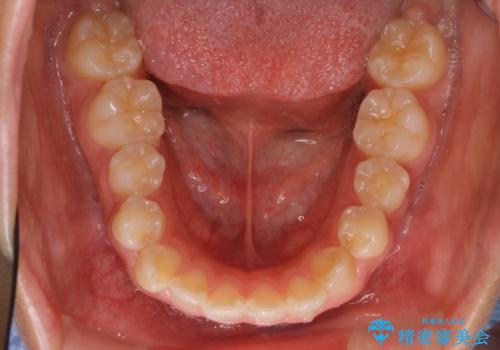

ハーフリンガル 半分裏側矯正による上下前突の抜歯矯正治療

- 矯正装置

- ハーフリンガル

- 上下左右4本の第1小臼歯を抜歯する、抜歯矯正を計画した。

抜歯矯正により前歯の位置が後ろに下がり、わずかではありますが、口元に改善がみられ、歯並びもきれいに整いました。